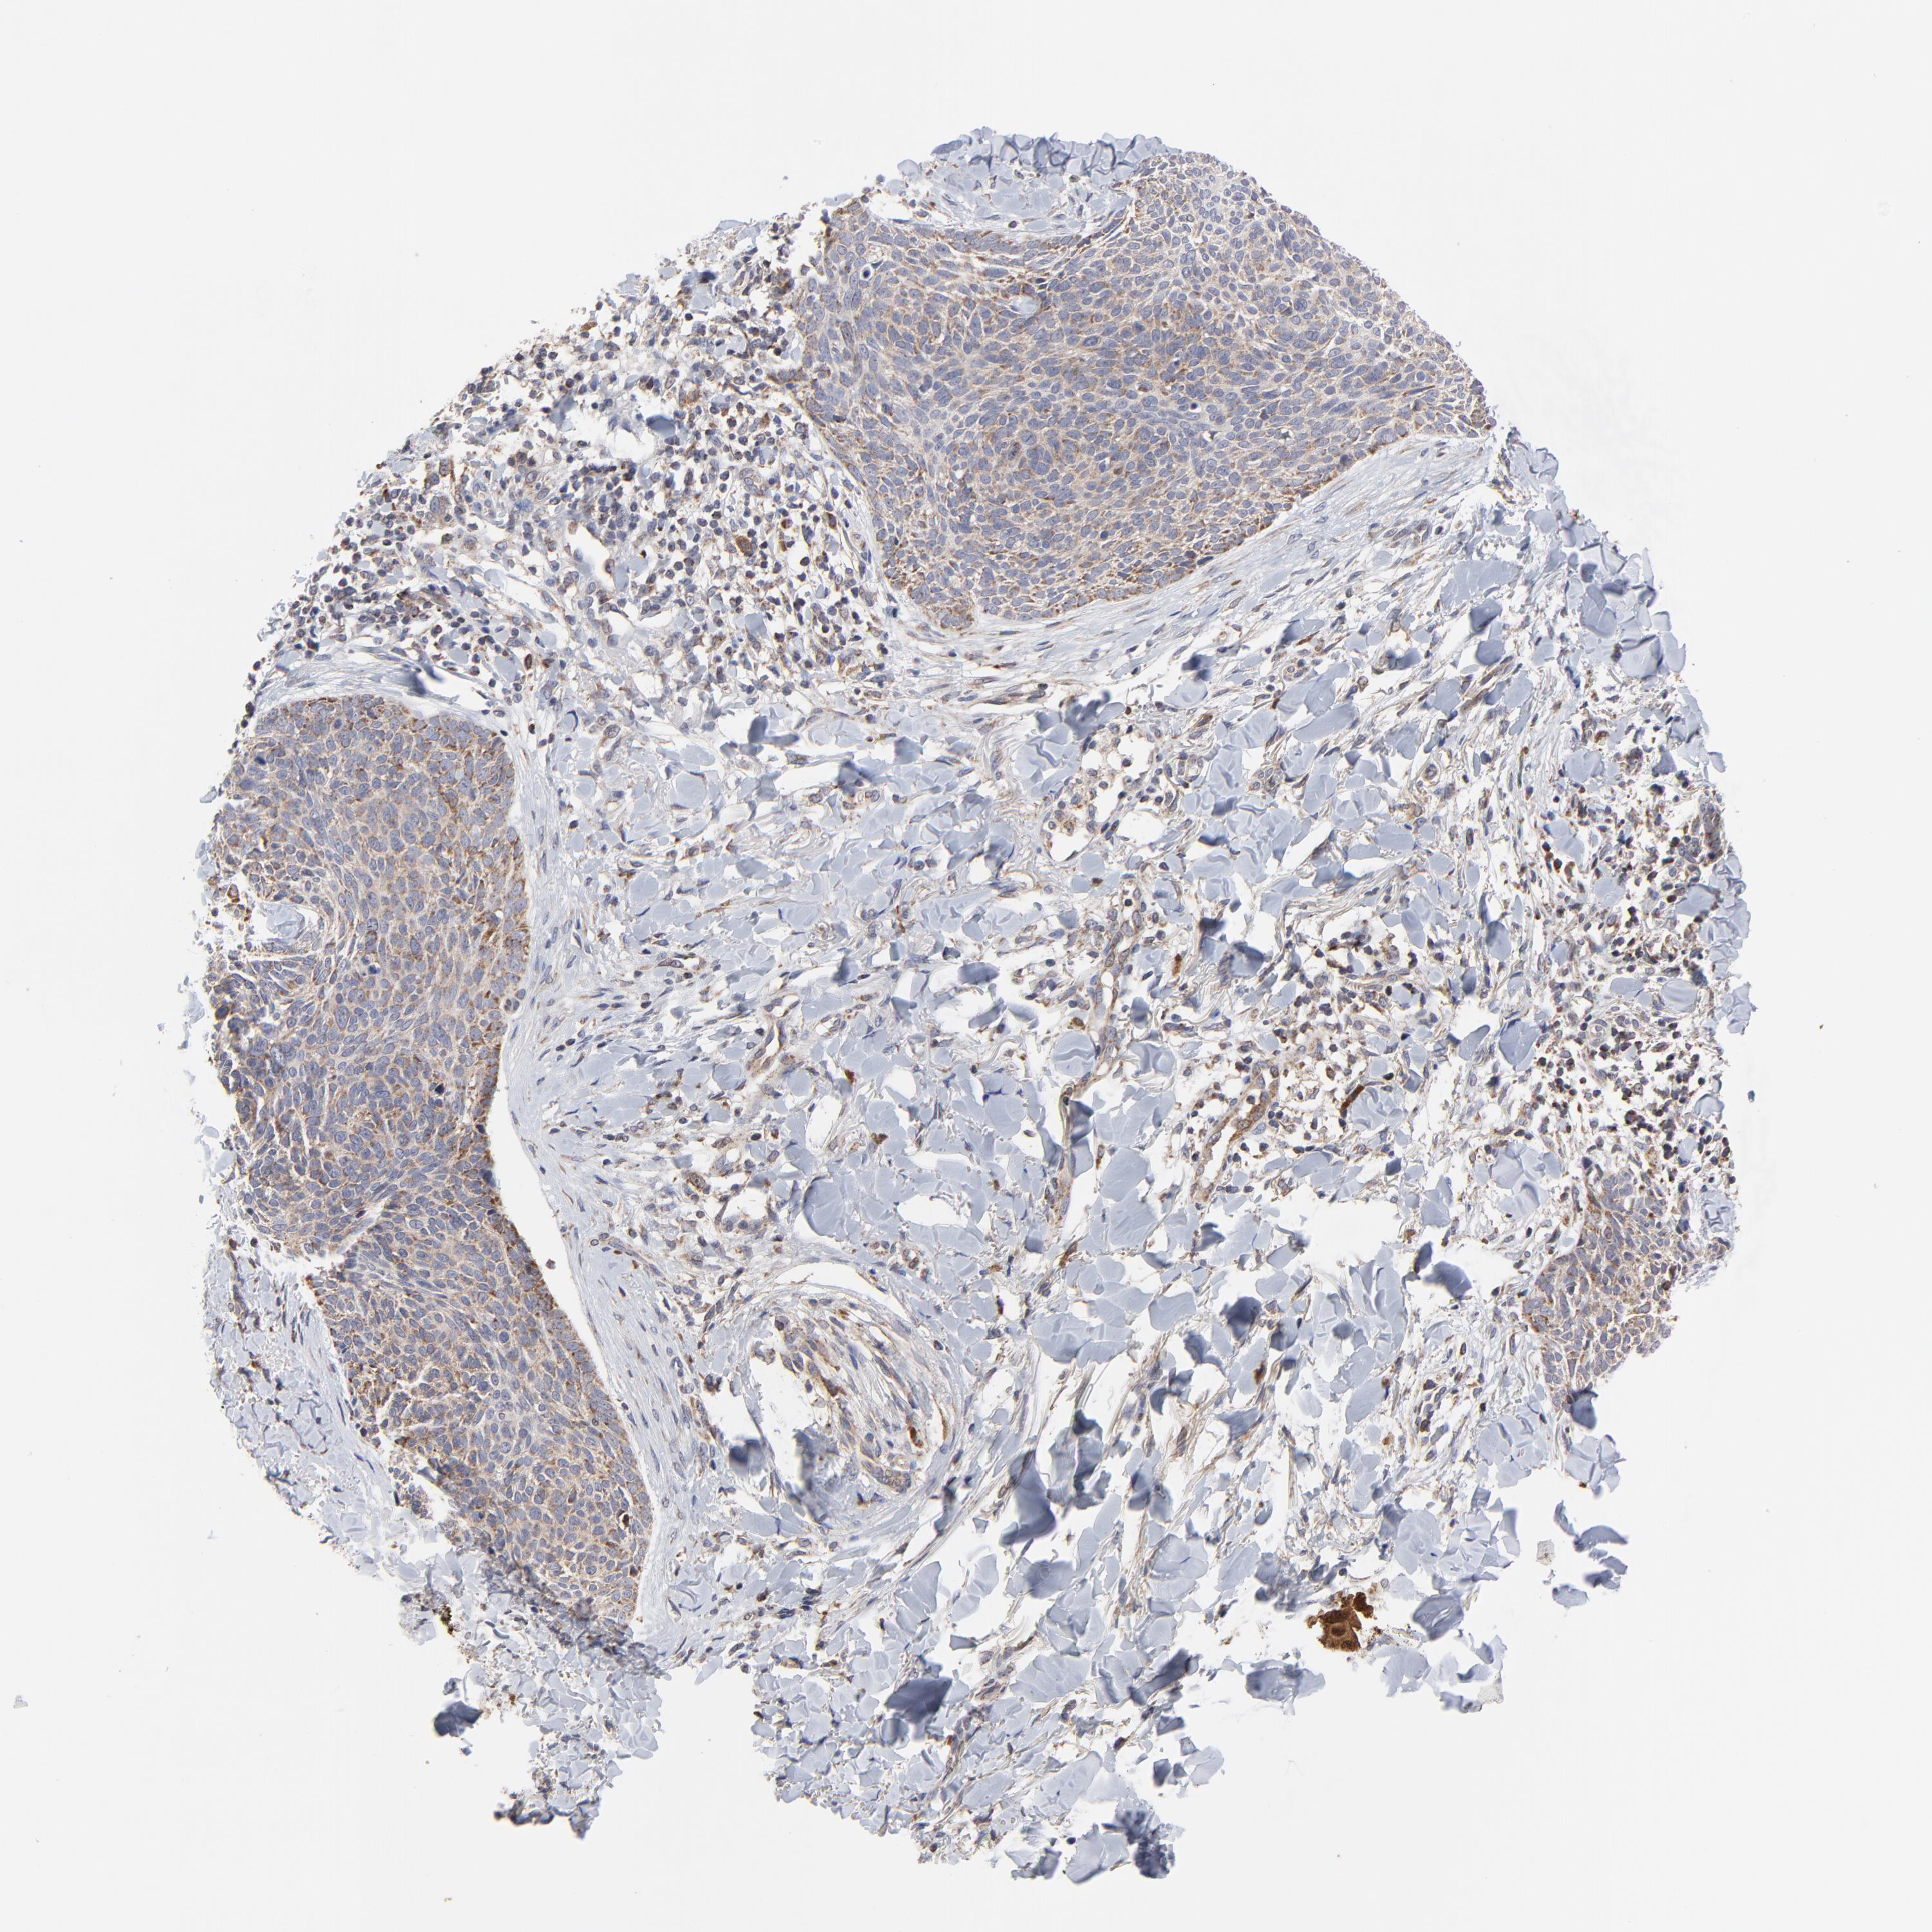

SKIN CANCER - Protein expressioni

A mouse-over function shows sample information and annotation data. Click on an image to view it in a full screen mode. Samples can be filtered based on level of antibody staining by selecting one or several of the following categories: high, medium, low and not detected. The assay and annotation is described here.

Antibody stainingi

Antibody staining in the annotated cell types in the current human tissue is reported as not detected, low, medium, or high, based on conventional immunohistochemistry profiling in selected tissues. This score is based on the combination of the staining intensity and fraction of stained cells.

Each image is clickable and will lead to virtual microscopy that enables deeper exploration of all samples and also displays staining intensity scores, fraction scores and subcellular localization as well as patient and tissue information for each sample.

Antibody HPA003251

Staining

High

Medium

Low

Not detected

Intensity

Strong

Moderate

Weak

Negative

Quantity

>75%

75%-25%

<25%

None

Location

Nuclear

Cytoplasmic/membranous

Cytoplasmic/membranous,nuclear

Squamous cell carcinoma, NOS

Basal cell carcinoma